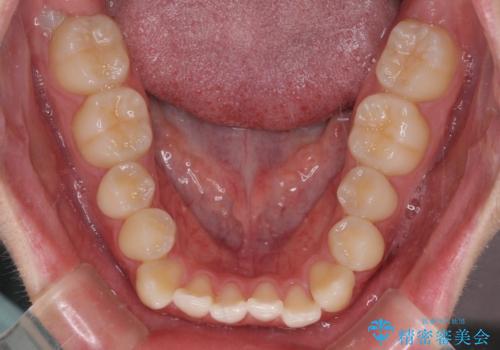

受け口傾向の骨格であり、前歯はクロスバイトまたは切端咬合となっており、叢生は警備であったため、下顎を中心に歯列全体の後方移動を行い、IPR(歯と歯の間を削る)によってデコボコが解消するように設計し、インビザラインにより治療を行うこととしました。

受け口傾向のインビザライン矯正は比較的治療を行いやすいため、きれいに仕上げることができました。舌の突出癖が顕著であったため、改善のためのトレーニングをしっかりと行っていただきました。